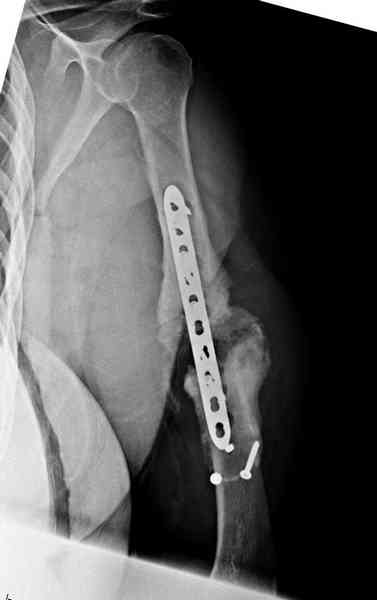

Как видно из выступлений коллег, способы фиксации

ложного сустава плеча могут быть различными, кто-то предпочитает аппаратом Илизарова (Соломин), пластинами (Волна) или интрамедуллярным гвоздем (Челноков).

Когда разбирался случай на сайте, и у нас была больная с похожей патологией, ложный сустав после поперечного перелома, леченного год назад где-то и кем-то в другом месте.

Мы не стали делать провокационный метод, который

предложил Корнеев для лечения - применение анаболических стероидов - ретаболила, из-за его бессмысленности, также не согласились с его теорией, что любая операция заблокирует суставы, а наоборот, провели жесткую фиксацию пластиной для раннего восстановления.

Первичную пластину убрали недели 6 назад из переднего оригинального доступа, и из-за подозрительности тканей вокруг пластины, решили провести реконструкцию поэтапно.

Хотя сам не стороннник применения более массивных

имплантов для плеча, но для этого случая сделали

исключение. На снимке 4А диаметр мягких ткани около 20 см, при весе больной более 135 кг, и также выступление Андрея Волны подстегнуло к применению более массивной 4.5 мм локинг пластины.